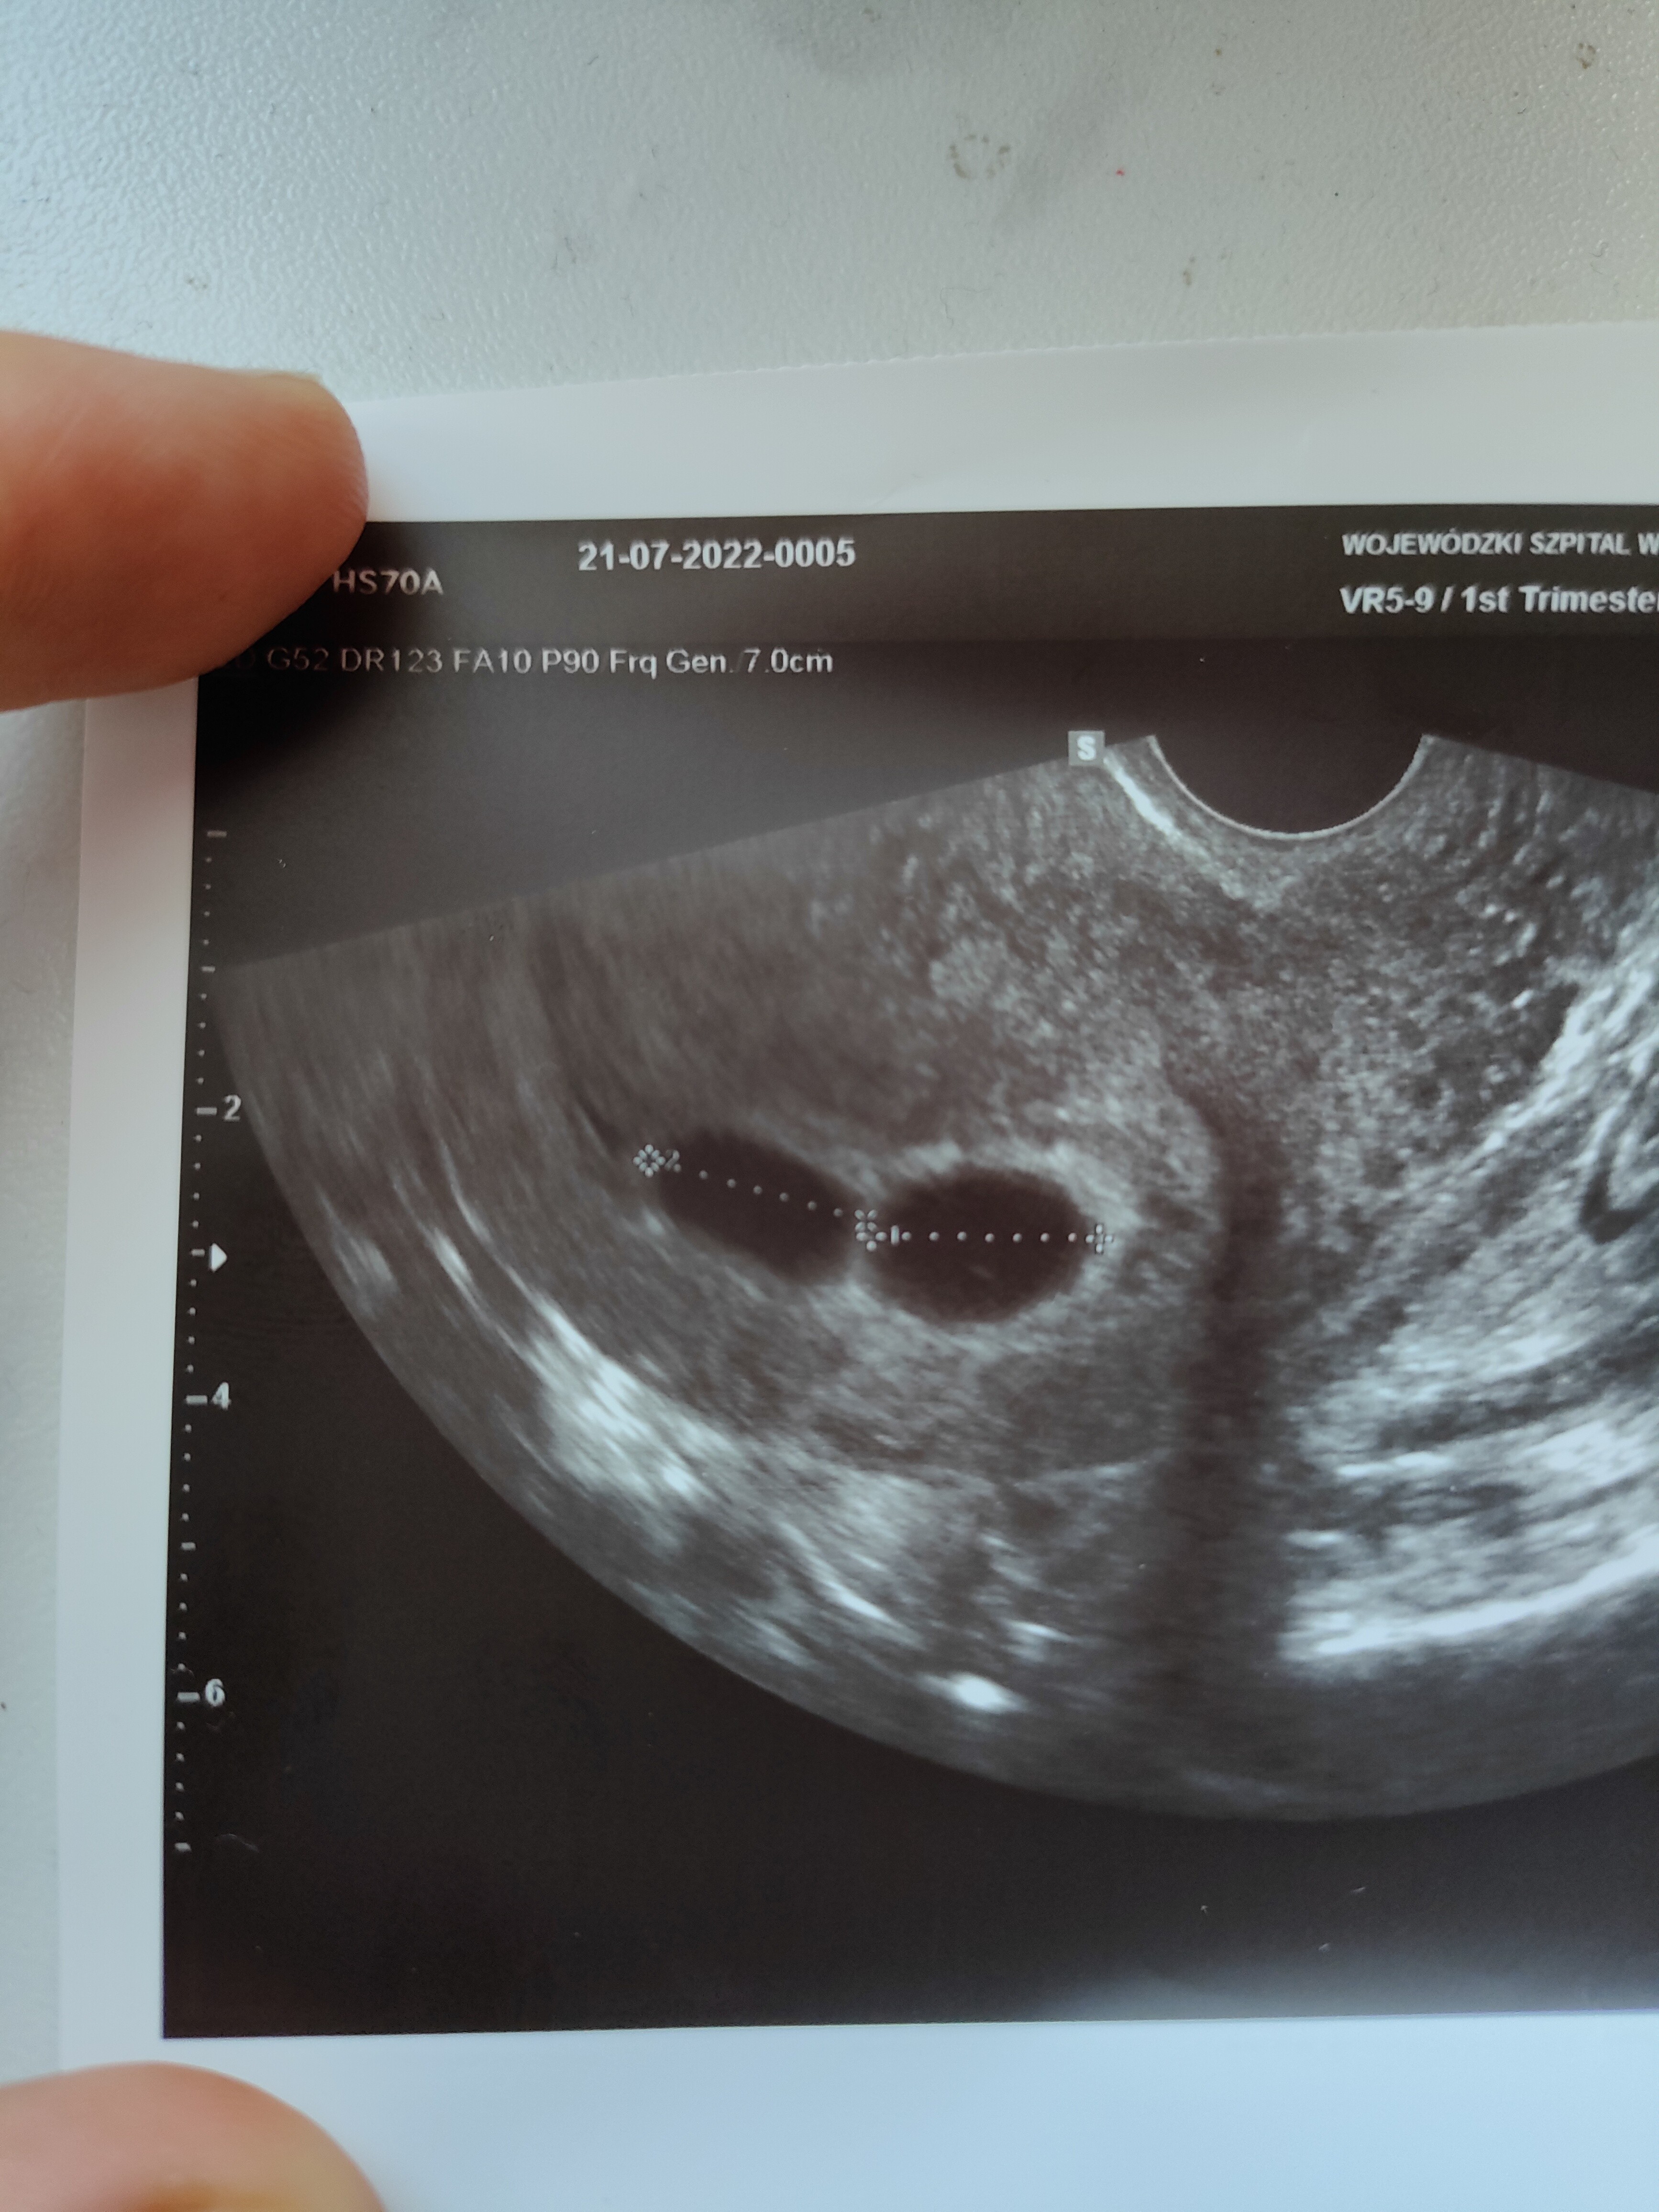

Chciałam się zapytać czy wiecie może czy na tym zdjęciu mogę już stwierdzić czy to ciąża bliźniacza dwujajowa czy jednojajowa?

To, że są dwa pęcherzyki nie świadczy o tym czy jest dwujajowe. Najważniejsze jest czy jest dwukosmowkowa i dwuowodniowa czy jedno. Ale to zbyt wcześnie, bardzo małe pęcherzyki, dopiero za jakiś czas uda się określić.

Chyba mylisz pojęcia. Skoro podałaś link to może się z nim zapoznaj co oznacza ciąża jedno czy dwujajowa. Na zdjęciu są ewidentnie dwa oddzielne pęcherzyki. Nie są ze sobą powiązane. Więc jak najbardziej są to bliźniaki dwujajowe.

Jesli chodzi o czytanie zdjęcia, to nie czuję, że mam kompetencję to odczytywania. Ale ze zdjęcia nie zawsze odczytasz "jajowość". Jedynie ilość owodni i kosmówek. I tak:

1 owodnia + 1 kosmówka = na pewno ciąża jednojajowa

2 owodnie + 1 kosmówka = na pewno ciąża jednojajowa

2 owodnie + 2 kosmówki = PRAWIE na pewno ciąża 2 jajowa

Rodzaj ciąży najlepiej widać w 9/10 tygodniu

Na pewno statystycznie większa szansa, że będą dwujajowe, ale jednak pęcherzyki bezpośrednio do siebie przylegają więc ja bym nie miała pewności 100%. Dla porównania u mnie wyglądało to tak- zobacz że pęcherzyki są mocno oddalone i tu jest pewność że ciąża dwujajowa ( procedura in vitro-miałam podawane dwa zarodki podczas transferu)